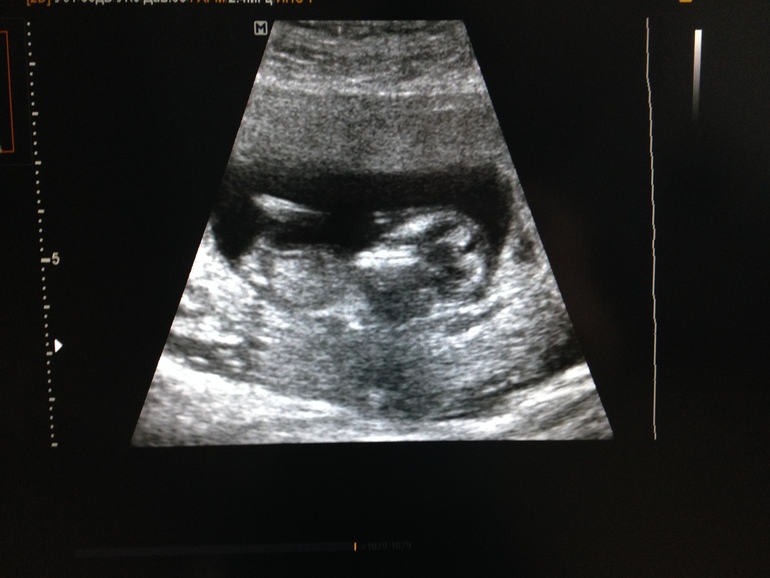

Эмоции под кат😊 Ожидая очередей я поплелась в соседнее здание на скрининг, но на удивление (или просто везучесть) я везде прошла первая и не сидела в очередях. УЗИ выдало такие показатели:

КТР - 55 мм (к слову 26 декабря на УЗИ он был 4,7 мм)

Что соответствует сроку 12 недель

ВП (я так понимаю это тоже самое что ТВП) - 1,6 мм

НК - 2 мм

Желточный мешок - 5 мм

Плацента по задней стенке 15 мм, б/о

Шейка матки до 34 мм

УЗИст сказала все хорошо, и пока не точно (срок то маленький) то мальчик!👶🏻

И на последок дали сфотографировать для папы нашего зайчика🐰